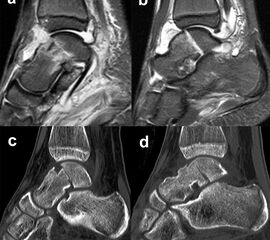

Eine exakte Abgrenzung von Taluskorpus- und Talushalsfrakturen ist allein anhand von Standard-Röntgenaufnahmen nicht sicher möglich. Inokuchi und Mitarbeiter definierten daher Talushalsfrakturen mittels CT, wobei die Frakturlinie distal vor dem Proc. fibularis talis ausläuft 6 (Abb. 1). Es ist anzunehmen, dass sich mit dieser Definition die oben angegebenen Zahlen von den Talushalsfrakturen etwas zu den Taluskorpusfrakturen verschieben, zumal diese mehrheitlich anhand von Röntgenaufnahmen erhoben wurden.

Prinzipiell werden konventionelle Röntgenaufnahmen vom OSG in 2 Ebenen (a.p. in 20° Innenrotation, „Mortise View“, und lateral) angefertigt (Abb. 1a, b). Zusätzlich können spezielle Projektionen wie die Canale oder Brodén-Aufnahme hilfreich sein, wurden in der klinischen Routine aber durch das CT oder DVT weitgehend verdrängt.

Bei in den konventionellen Aufnahmen nicht sicher auszuschließender Talusfraktur bzw. zur genauen Darstellung der Dislokation bei Taluskorpus- oder Talushalsfraktur sollte die Indikation zur CT-Diagnostik großzügig gestellt werden (Abb. 1 c, d). Insbesondere dient die CT-Diagnostik zur genauen Evaluierung der Frakturmorphologie und OP-Planung sowie auch zur Vermeidung möglicher übersehener peripherer Talusfrakturen 4.